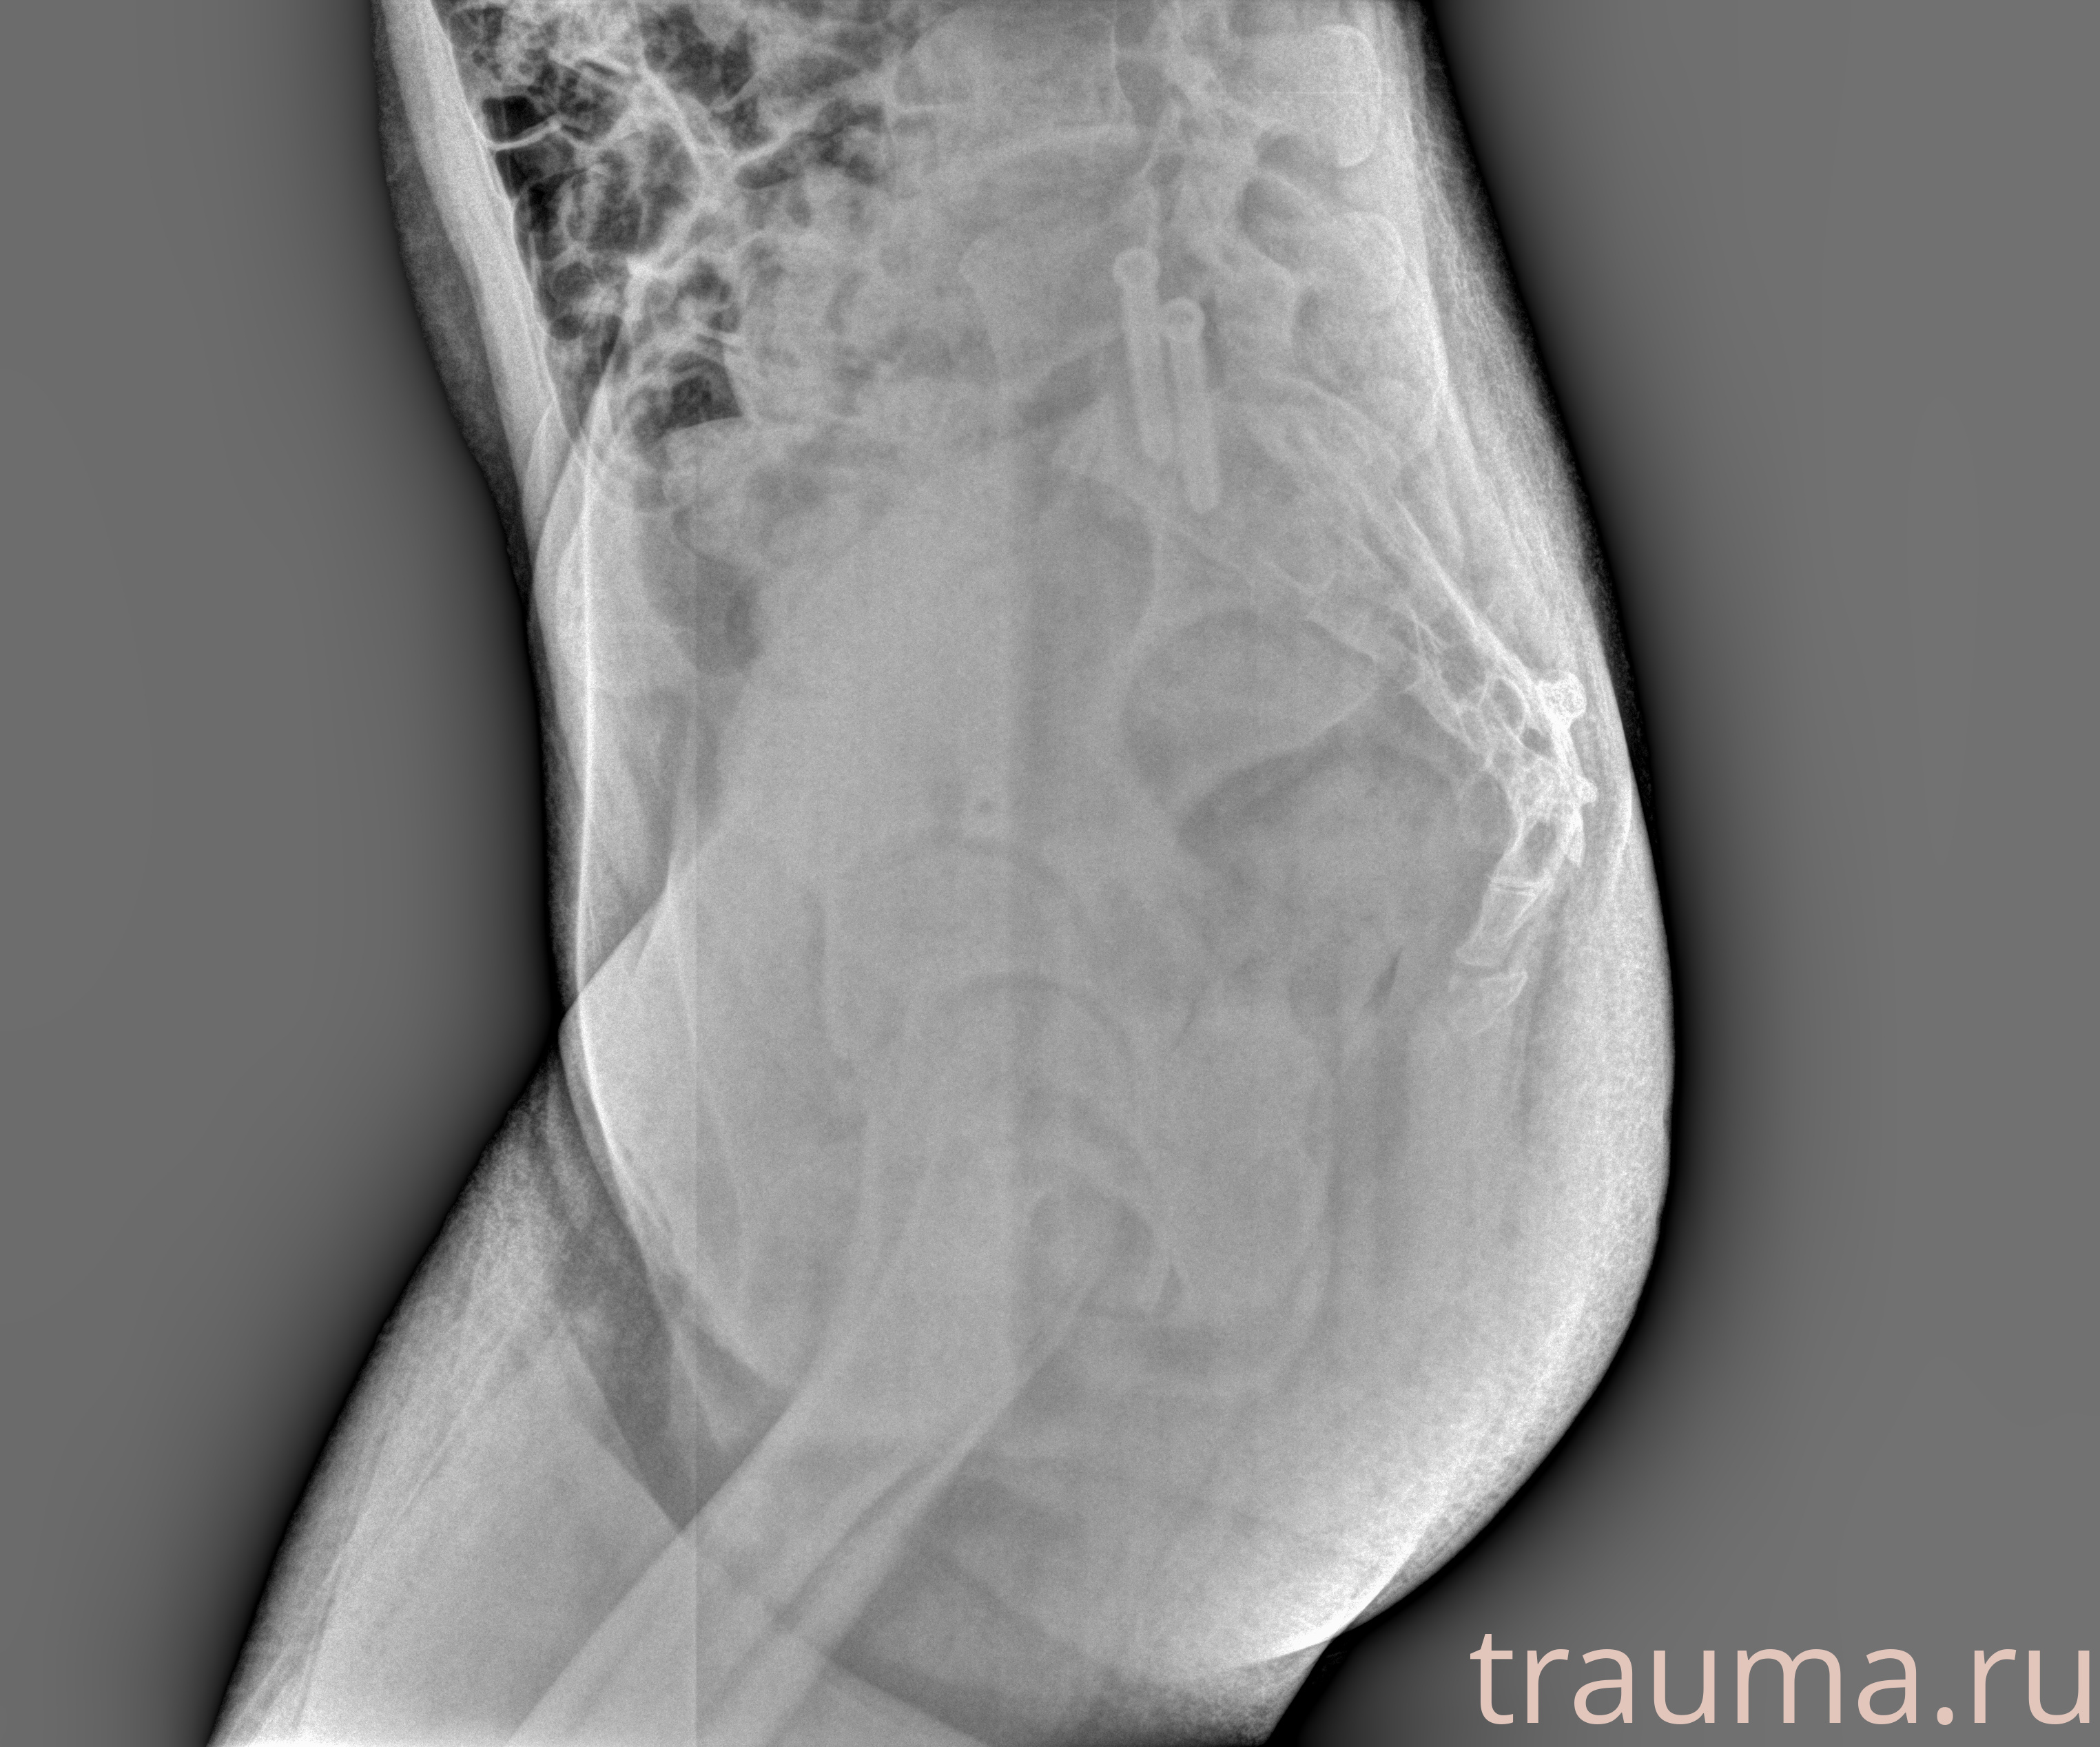

Рентген на дому: по вашему адресу приезжает врач-рентгенолог, травматолог-ортопед с мобильным рентгеновским аппаратом, проводит диагностику травмы или заболевания, делает необходимые рентгенограммы, дает рекомендации по дальнейшему лечению. Получить качественные снимки в домашних условиях возможно благодаря уникальной методике, разработанной МосРентген Центром для института  Склифосовского